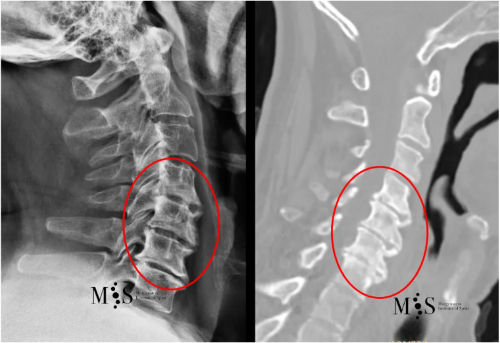

TAC (izquierda) y Rx (derecha) de columna cervical que muestra una degeneración avanzada de

varios discos intervertebrales cervicales (marcados con un círculo rojo).